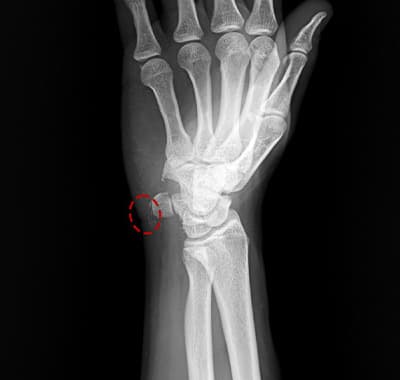

타병원 3회 시술에도 제거되지 않은 석회 (내원 당시)

실제 환자 사례

“다른 병원에서 석회 빼는 시술을 3번이나 받았는데, 아직도 그대로래요. 시술받고 나면 오히려 더 아프고. X-ray 찍어보니 석회가 거의 그대로였습니다. '석회가 너무 단단해서 주사로는 안 빠진다, 수술해야 한다'고 하더라고요.”

— 40대 초반 여성 환자, 플래티넘의원 내원

단단한 석회 = 방법의 문제

1~2세대 방식(세척술·주사흡입술)은 물렁한 석회에만 효과적입니다. 3세대 분쇄흡입술은 석회를 물리적으로 갈아내기 때문에, 아무리 단단해도 1회에 완전 제거가 가능합니다.